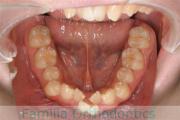

上顎

下顎

前歯の関係など

右側

正面

左側